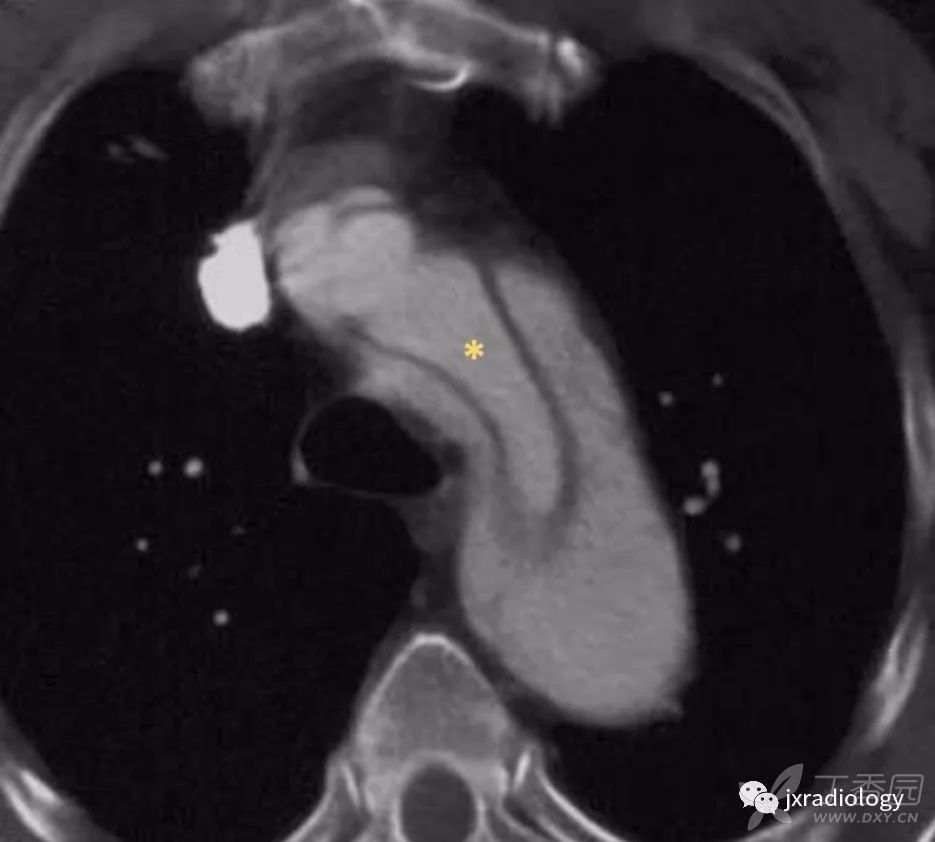

Stanford A型主动脉夹层患者出现急性心包积液时提示高死亡率,与心包填塞有关( 图16 )。

图16:平扫CT显示自发性高密度心包积液,符合心包积血(a图星号)。双侧胸腔积液可见。增强后示Stanford A型主动脉夹层,并出现假腔的局部血栓形成(b图箭头)。